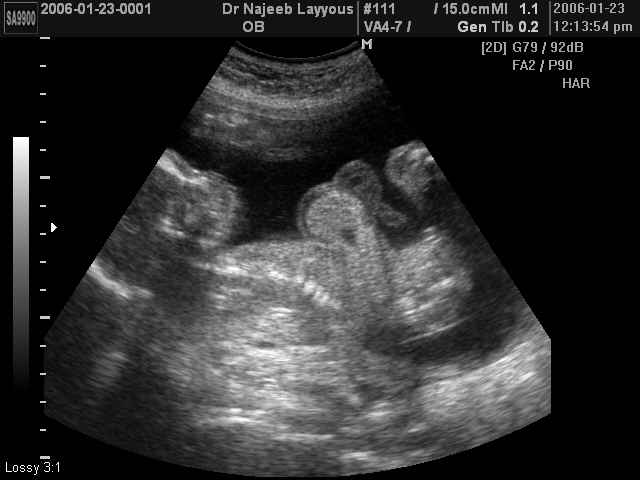

صور طبية للحمل بجهاز الالتراساوند | الدكتور نجيب ليوس